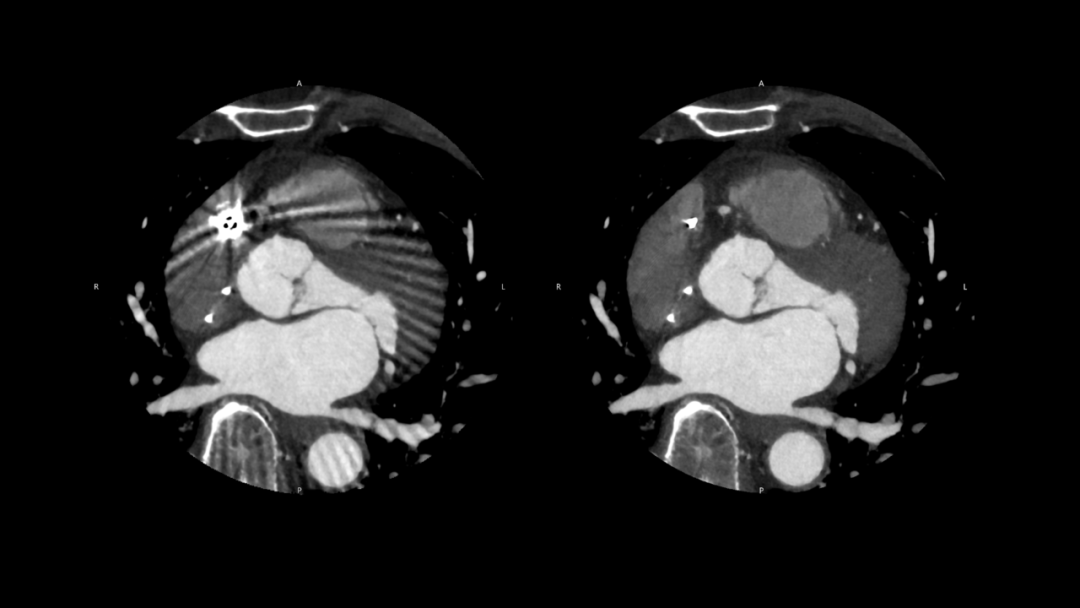

🔹在心血管成像中,CZT-PCCT通过更高的空间分辨率与更薄层厚成像能力,使血管细节及远端分支结构获得更清晰、连续的显示。对于小血管及复杂病变的观察,有助于提升影像评估的精细度,为心血管疾病的诊断与分析提供更加可靠的依据。

在心血管成像中,针对支架、起搏器等金属植入物带来的伪影影响,结合PIQE超分辨重建与SEMAR金属伪影抑制技术,可在不增加辐射剂量的前提下减少金属伪影对图像的影响,提升周围软组织的显示效果,从而为复杂病例提供更清晰、可靠的影像参考。